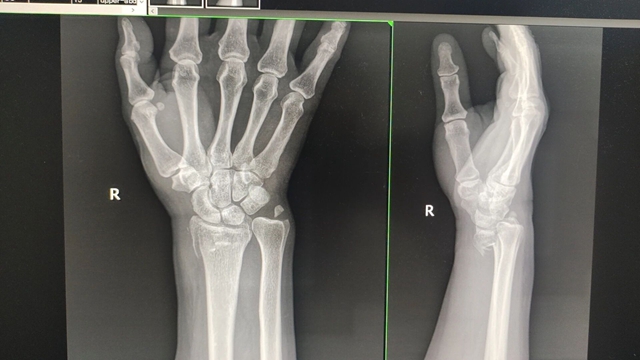

梁女士受伤时X片

50岁的梁女士伤情最重,她骑电瓶车时不慎与小车发生剐蹭,右手着地导致右手骨折,急诊医生为其进行了手法复位,但效果不理想,建议她手术治疗。梁女士不甘心,经朋友介绍,找到了西南医科大学附属中医医院正骨病房。